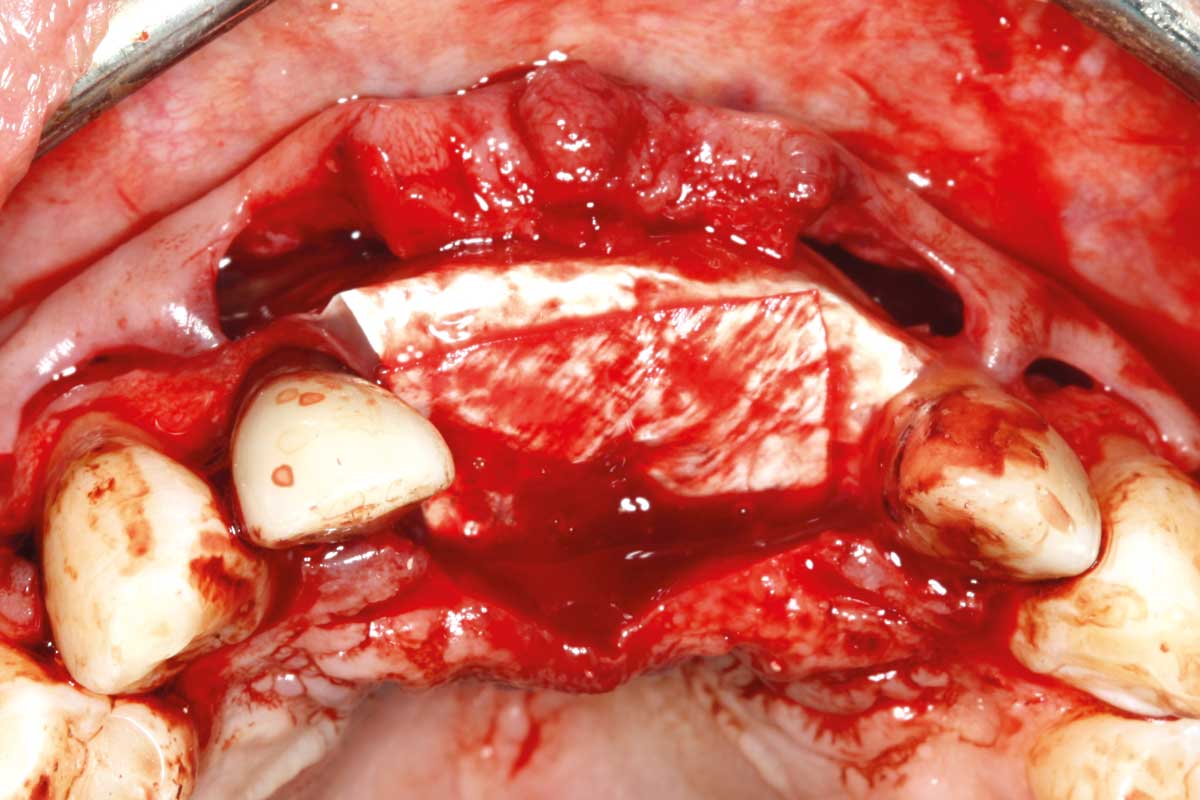

04/26 - Combined vertical and horizontal bone defect in area 21

Ridge augmentation in the maxilla with maxgraft® bonebuilder in the aesthetic zone - Dr. M. Kristensen